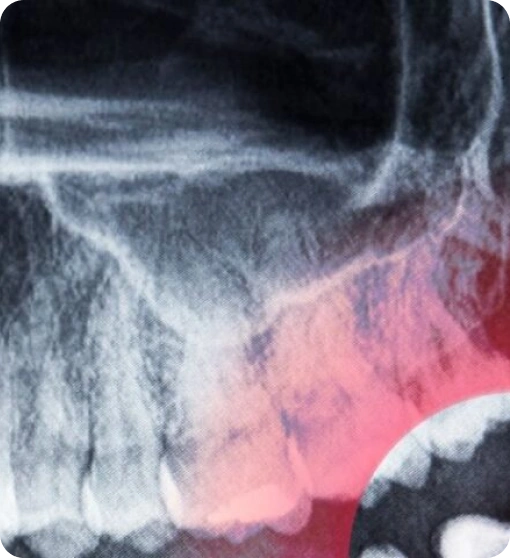

Die 3D – Röntgendiagnostik hat die Zahnmedizin revolutioniert, indem sie eine präzise und exakte Darstellung der zahnmedizinischen Strukturen ermöglicht. Mit der Volumentomographie (DVT), einem speziellen Verfahren zur dreidimensionalen Röntgenaufnahme, können Zahnärzte wichtige Informationen über Zähne, Kiefer und umliegende Gewebe erhalten. Diese innovativen CT-Techniken reduzieren die Strahlenbelastung für Patienten im Vergleich zu herkömmlichen Röntgenaufnahmen und gewährleisten gleichzeitig eine genaue Untersuchung. Insbesondere bei der Planung von Behandlungen, wie etwa bei der Implantation im Alldent Zahnzentrum, sind die dreidimensionalen Aufnahmen unerlässlich für die Diagnose und die erfolgreiche Behandlung.

Die 3D – Röntgendiagnostik ist ein modernes Verfahren in der Zahnmedizin, das insbesondere durch die Digitale Volumentomographie (DVT) geprägt ist. Bei dieser Technik werden dreidimensionale Aufnahmen der Zähne und Kiefer gemacht, die eine exakte Darstellung der anatomischen Strukturen ermöglichen. Im Gegensatz zu herkömmlichen Röntgenaufnahmen bietet die Computertomographie (CT) eine präzisere Untersuchung, die für die Diagnose und Planung von Behandlungen, wie zum Beispiel das Setzen von Implantaten, entscheidend ist. Dabei wird die Strahlenbelastung für die Patienten minimiert, während gleichzeitig eine detaillierte Abbildung der zahnmedizinischen Gegebenheiten gewährleistet wird.

Die 3D – Röntgendiagnostik , auch bekannt als DVT (Digitale Volumentomographie), bietet zahlreiche Vorteile für Patienten und Zahnärzte. Durch die dreidimensionale Darstellung der Zähne und Kiefer werden wichtige Strukturen exakter abgebildet als bei herkömmlichen Röntgenverfahren. Dies ermöglicht eine präzisere Diagnose und zielgerichtete Untersuchung, insbesondere bei der Planung von Implantaten. Zudem reduziert die Strahlenbelastung im Vergleich zur klassischen CT die Risiken für die Patienten erheblich. Daher ist die 3-D Röntgendiagnostik eine wertvolle Ergänzung in der zahnmedizinischen Diagnostik.

Die 3D – Röntgendiagnostik beim Zahnarzt beginnt mit der Vorbereitung des Patienten, der in einen speziellen Röntgenraum geleitet wird. Dort wird der Kopf stabilisiert, um präzise Aufnahmen zu gewährleisten. Der Zahnarzt oder das Fachpersonal aktiviert das Röntgengerät, welches in wenigen Sekunden eine umfassende 3-D Aufnahme des Kiefers und der Zähne erstellt. Diese hochauflösenden Röntgenbilder ermöglichen eine detaillierte Analyse von Zahn- und Kieferstrukturen, was eine optimale Diagnostik und Behandlungsplanung unterstützt.

Die Durchführung des 3D – Röntgen erfolgt in der Zahnarztpraxis mithilfe eines speziellen Röntgengeräts, das eine dreidimensionale Darstellung der Zähne und des Kieferbereichs ermöglicht. Der Patient wird in einer aufrechten Position platziert, während das Gerät um den Kopf rotiert und mehrere Röntgenbilder aufnimmt. Diese Bilder werden anschließend digital verarbeitet und zu einem präzisen 3-D-Modell zusammengesetzt. Dieses Verfahren erlaubt eine detaillierte Analyse von Knochenstrukturen, Zähnen und möglichen Pathologien, was die Diagnostik und Planung von Behandlungen erheblich verbessert.